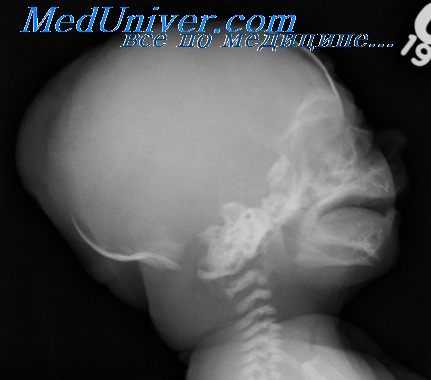

Окостенения преобладающей части хрящевого примордиального черепа на третьем месяце развития еще не произошло. Лишь большие крылья основной кости, центральный отдел затылочной кости и небольшие участки в ее латеральной части образованы костью. И у новорожденного сращены еще не все части; окончательное сращение происходит в течение нескольких лет в процессе внеутробной жизни.

Все эти образования в результате десмогенного окостенения разрастаются из соответствующих центров в плоскости, а их края взамно сближаются, соединяясь, наконец, узкими соединительнотканными полосками, из которых между ними развиваются швы (saturae). Однако это соединение и у новорожденного еще не совершенно (рис. 170); кости у него еще не подходят вплотную одна к другой; таким образом, между костями возникают неокостеневшие перепончатые, мягкие спайки, так называемые роднички (fonticuli — фонтанеллы). В месте пересечения чешуи затылочной кости с обеими теменными костями (область стыка сагиттального, стреловидного шва с лямбдовидным швом) располагается малый, или затылочный, родничек (fonticulus minor, occipitalis).

Несколько кпереди на месте пересечения сагиттального шва со швом венечным, между лобной костью и теменными костями, располагается большой родничек (fonticulus major, frontalis), который полностью зарастает лишь на третьем году жизни. Лобные кости срастаются раньше (приблизительно в течение второго года жизни) в единую, лобную кость (os frontale). Между нижним отделом чешуи затылочной кости и с другой стороны чешуи височных костей находится сосцевидный родничек (fonticulus mastoideus), который также закрывается на втором году жизни. Подобным образом между вентролатеральной частью теменной кости и большими крыльями основной кости располагается основной, или клиновидный, родничек (fonticulus sphenoi-deus), исчезающий в результате сращения костей на третьем году жизни.

Тот факт, что отдельные кости у новорожденного еще полностью не сращены, и между ними находятся упомянутые роднички и соединительнотканные швы, обусловливает взаимную подвижность костей. Это имеет большое значение во время родов, когда при прохождении головки плода по родовому каналу необходимо хотя бы частичное приспособление конфигурации черепа плода форме родовых путей.